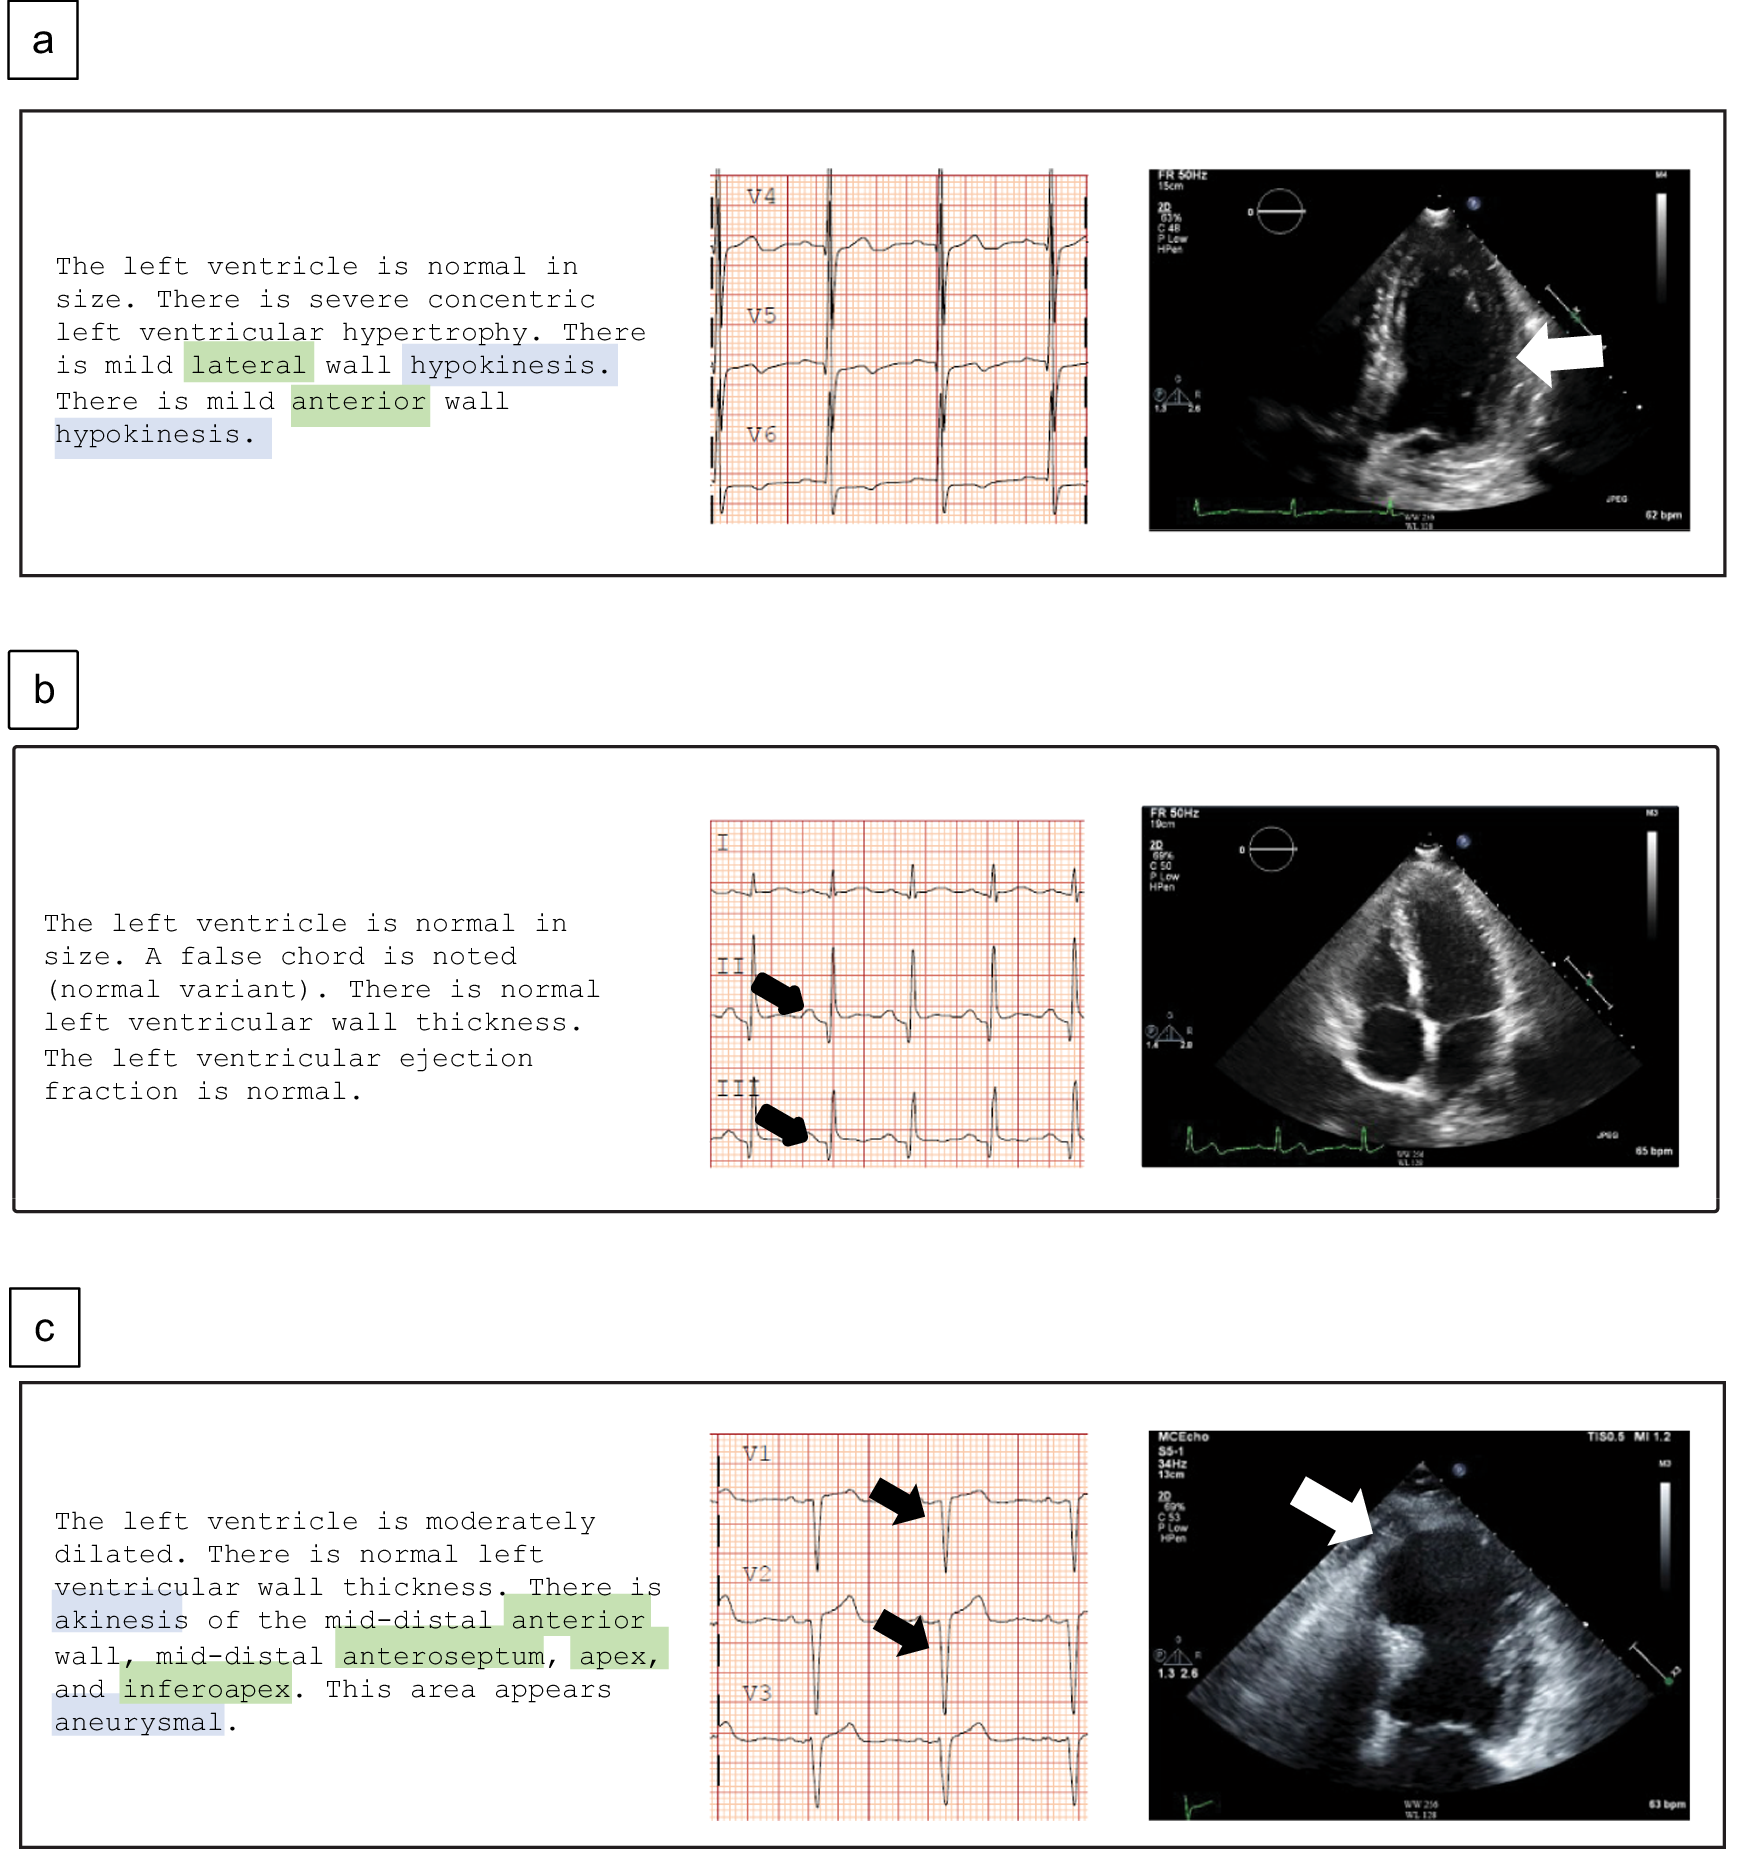

Fig. 2: Representative cases of ECG and echocardiographic studies with and without WMAs detected by ECG-WMA-Net.

a A black man in his sixties without Q waves on ECG but with mild anterior and lateral WMA (white arrow) (ECG-WMA-net true positive). b A Hispanic man in his forties with Q waves on ECG but without WMAs on echocardiogram (ECG-WMA-Net true negative). c A female in her sixties with anterior and lateral Q waves (black arrows) on ECG and akinesis of the apex and mid-distal anterior and inferior walls (white arrow). Green text highlights show language tagged for location, and blue text highlights show language tagged for abnormalities.